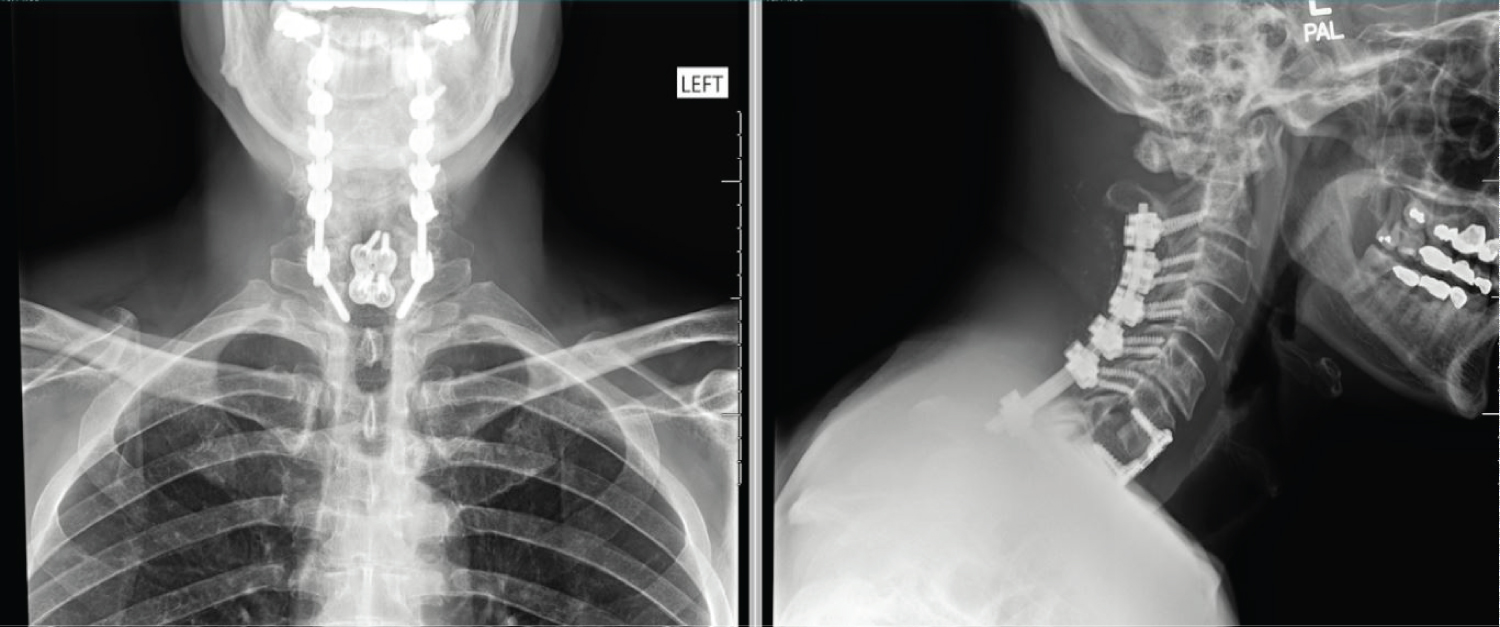

The patient initially presented to emergency department with progressive upper and lower extremity weakness. Physical exam revealed right greater than left upper and lower extremity weakness, radiculopathy and decreased sensation in bilateral upper extremities and hyperreflexia in the right lower extremity. Neurosurgery recommended MRI under sedation or CT myelogram, which the hospital does not perform. He was transferred to another facility with those capabilities. The patient presented to the ED with physical exam significant for signs of cervical myelopathy. He exhibited Hoffman's sign bilaterally, clonus in the right ankle, and hyperreflexia in upper and lower extremities bilaterally. Babinski was absent. Weakness in right hand and lower extremity was seen on motor exam (Table 2). MRI of the cervical, thoracic, and lumbar spine were performed under sedation. It displayed severe cervical degenerative disease spanning from C2-C7, ossification of the posterior longitudinal ligament of the C5-C6 segment, and severe spinal canal stenosis with moderate to severe cord compression from C5-C6, C6-C7 (Figure 1 and Figure 2). Two hours after the initial MRI, the patient developed sudden onset right leg plegia and worsening motor weakness in his right hand (Table 3). A repeat MRI was performed and revealed a hyperacute hemorrhage surrounding the extruded C6-C7 disc was revealed through T1 weighted imaging. The patient underwent an emergent anterior posterior cervical decompression fusion involved laminectomy's from C3-7 and a posterior fusion with pedicle screws from C2-T1 (Figure 3). On postoperative day 6, there was some improvement in neurology, with a returning of lower extremity strength from 0/5 to 4/5 (Table 4). During a follow-up of 3 months after discharge, the patient reported relief of pain and full return of sensory and motor deficits.

Figure 3: Post-operative AP and lateral view X-rays after posterior instrumented fusion C2-T1 and anterior interbody fusion C6-C7. Decompression was performed posteriorly C3-C7 and anteriorly C6-C7. View Figure 3